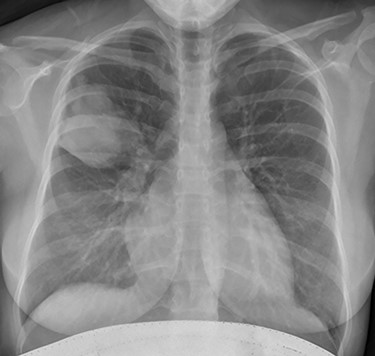

The case was rediscussed at the lung multidisciplinary meeting, and the plan was for the patient to undergo thoracic surgical intervention to remove the mass due to its uncertain nature. As the patient had remained asymptomatic with no haemoptysis and there was no interval change in the mass on surveillance imaging, the patient was brought back for follow-up bronchoscopy. This demonstrated evidence of a previous inflammatory process with cavitation and destruction of sub-lobar bronchial tree. Impression was that the last bronchoscopy had cleared the airway and the patient coughed and cleared the lung distally. The procedure was largely uncomplicated. The patient was subsequently discharged after they had recovered from the anaesthetic. Serial chest radiographs demonstrated almost complete resolution of the right upper lobe mass (Fig. 4). Furthermore, serial IgE titres demonstrated decreasing levels, and this was without the patient being commenced on any antifungal treatment.

Plain chest radiograph demonstrating resolution of the right upper zone mass.